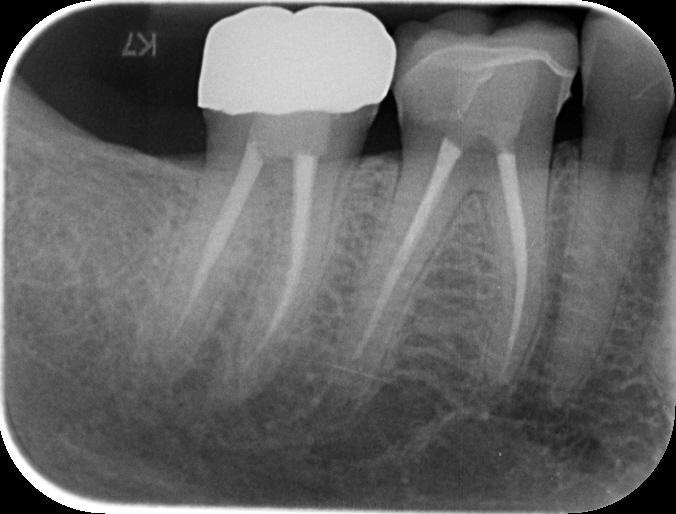

His previous dentist retired, and the patient visited me for the first time as an emergency visit due to symptomatic irreversible pulpitis from a cracked tooth (46). Root canal treatment on tooth 46 was completed, and a crown placed.

To better understand the patient's overall dental health, a full mouth CBCT scan was taken, confirming the presence of a bony defect in the area where tooth 24 had been surgically extracted.

Pre-surgical planning began with acquiring high-quality diagnostic data, including TRIOS intraoral scans and CBCT imaging. The data was imported into 3Shape Implant Studio, where I designed a virtual crown for tooth 24 and planned the precise positioning of the implant, considering critical factors such as sinus proximity, adjacent roots, bone density, and the location of the bony defect.

A radiographic assessment confirmed the proper integration and positioning of the implant.